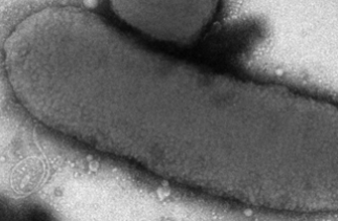

Une nouvelle venue dans le monde des bactéries. Les experts de l’Institut Pasteur, à Paris, ont identifié la bactérie responsable du décès de trois nourrissons à Chambéry (Savoie), en décembre 2013. Ils décrivent la fraîchement nommée Rouxiella chamberiensis dans l’International Journal of Systematic and Evolutionary Microbiology.

4 nourrissons hospitalisés au service de réanimation néonatale de Chambéry ont été infectés par Rouxiella chamberiensis. Le choc septique tue 3 d’entre eux en quelques jours. Au moment des faits, les poches de nutrition sont rapidement mises en cause. La Cellule d’intervention biologique d’urgence (CIBU), de l’Institut Pasteur, est sollicitée. Elle identifie 6 poches de nutrition parentérales contaminées. Mais la bactérie n’appartient à aucun genre connu. L’équipe de Jean-Claude Manuguerra la baptise donc.

Depuis décembre 2013, l’équipe de l’Institut Pasteur a réalisé le séquençage complet du génome de Rouxiella chamberiensis. Désormais reconnue par le Comité international de taxonomie bactérienne, elle possède des caractéristiques particulières. « De manière étonnante, elle se multiplie à 4°C, alors que la plupart des entérobactéries sont incapables de se développer en-dessous de 8°C. De plus, elle se met en latence et cesse sa croissance à 37°C », explique l’Institut Pasteur.